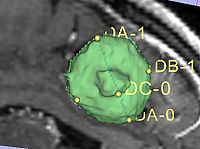

- Implementation details The module implements the following algorithm for calculating the dimensions of the label. First, the area of the label slice is computed in all the slices of the image that are passing through the label. This is done for the three orthogonal directions of the image. The largest area slice is found. The largest diameter (DA) is estimated by finding the two most distant points on the contour of the label cross-section. The second diameter (DB) is found by finding the two most distant points on the contour that lie on the line perpendicular to the first diameter. The third diameter (DC) is estimated by calculating the two points of intersection between the line perpendicular to the plane formed by DA and DBpassing through the point of their intersection, and the contour of the analyzed label.

The module also outputs numeric values for the lengths of the computed diameters. To see these numbers, open Log Viewer, and select the first from top log record with the name Label Diameter Estimation: standard output. The reported numbers are the lenghts of the three diameters, the volume estimate calculated as A*B*C/2 (a formula suggested in the literature for estimating volume of hematomas from planimetric measurements [2]), and the true label volume in mm^3. |